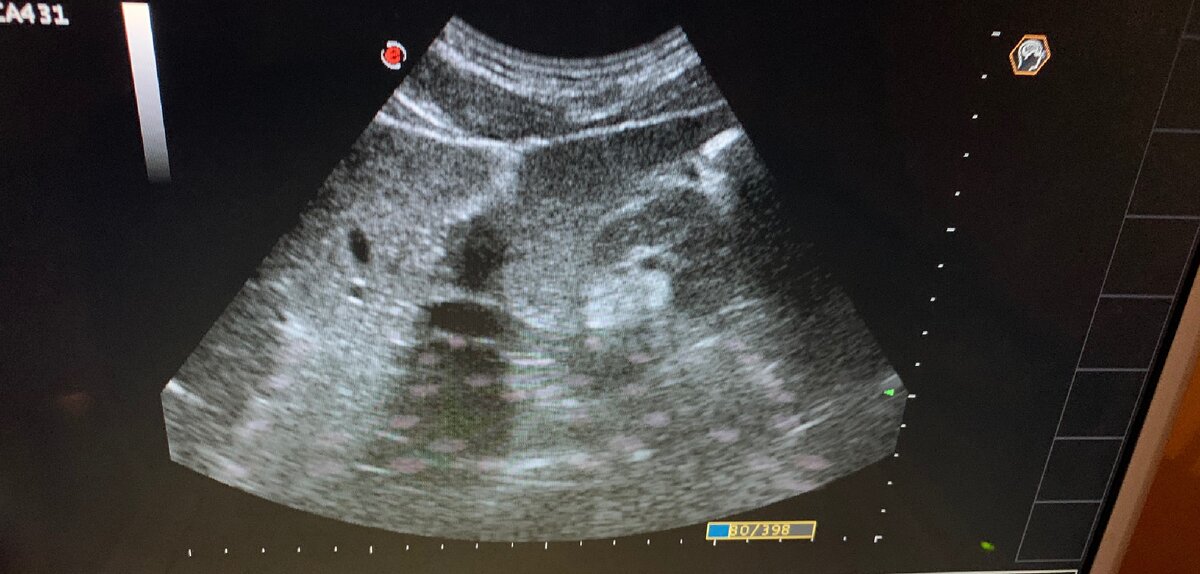

Слева на Узи- киста печени, справа- признаки гемангиомы

При проведении УЗИ пациентке я обнаружила три гиперэхогенных образования в правой доле печени, с четким ровным контуром, однородной структуры. Такая картина характерна для доброкачественных гемангиом.

Гемангиома - это доброкачественная сосудистая опухоль.